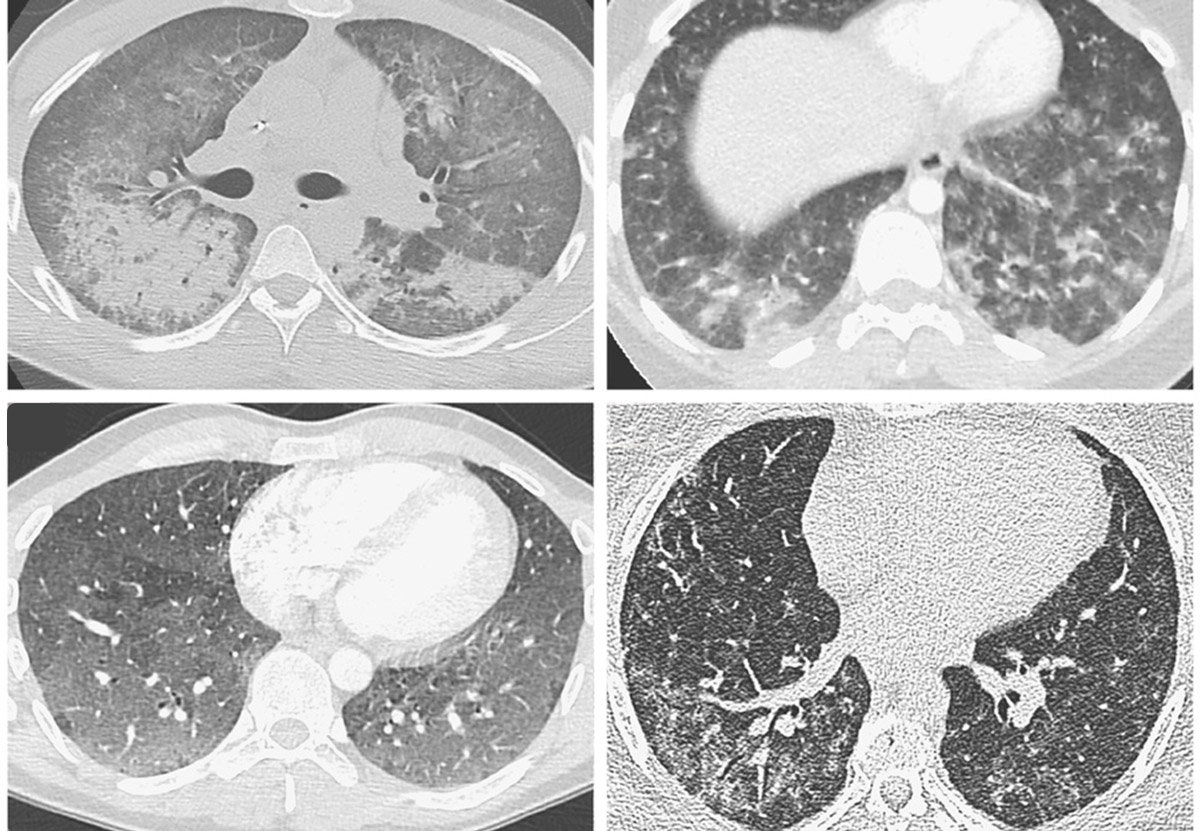

Pulmoner Boyut: EVALI ve Kardiyovasküler Etkileşim

EVALI (E-cigarette or Vaping Associated Lung Injury), e-sigara kullanımına bağlı gelişen akut akciğer hasarıdır ve özellikle 2019 yılında tanımlanan olgularla dikkat çekmiştir (6). Kardiyovasküler açıdan değerlendirildiğinde, EVALI’ye eşlik eden sistemik inflamatuvar yanıt ve hipoksemi; özellikle altta yatan kardiyak hastalığı bulunan bireylerde akut koroner sendrom ve aritmi riskinde artışa yol açabilecek önemli patofizyolojik mekanizmalar olarak öne çıkmaktadır (7).